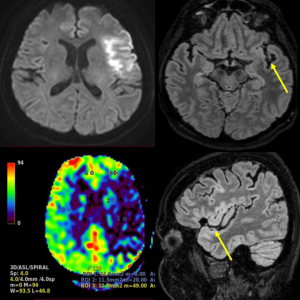

The FLAIR sequence often demonstrates the extent of acute stroke (considered beyond potential salvation); however, it takes several hours for the infarcted parenchyma to become hyperintense. A more precocious finding is represented by the FLAIR hyperintense vessel sign (FHVs), corresponding to vessels situated downstream an arterial occlusion.3 This sign is often readily identifiable on the FLAIR sequence considering the low signal from surrounding cerebrospinal fluid.

Moreover, a more recent study attempted to nuance the leptomeningeal collateral status by analysing the pattern of FHVs with regard to initial DWI lesion extent.5 Thus, in patients with FHVs situated inside the borders of the DWI lesion, regional cerebral blood flow and volume as well as collateral grade were significantly lower on the CTA/CTP examination than in patients with FHVs identified outside of the lesion. The authors suggested that the FHVs-out pattern may represent a cerebral perfusion reserve stage,5 being associated with relatively improved cerebral perfusion and thus, adequate, but temporary leptomeningeal collaterals.

In summary, the FHVs is a precocious radiological marker identified on MRI FLAIR sequence, demonstrating an alteration of cerebral hemodynamics downstream a severe stenosis or occlusion. It is generally believed to represent an area of ischaemic penumbra (and thus with salvageable potential), probably stemming from insufficient or temporary leptomeningeal collateralisation. Lastly, its prognostic value seems to be dependent on its relationship with the DWI lesion extent, with FHVs situated outside of positive DWI lesions being most informative of the reserve of salvageable cerebral tissue.